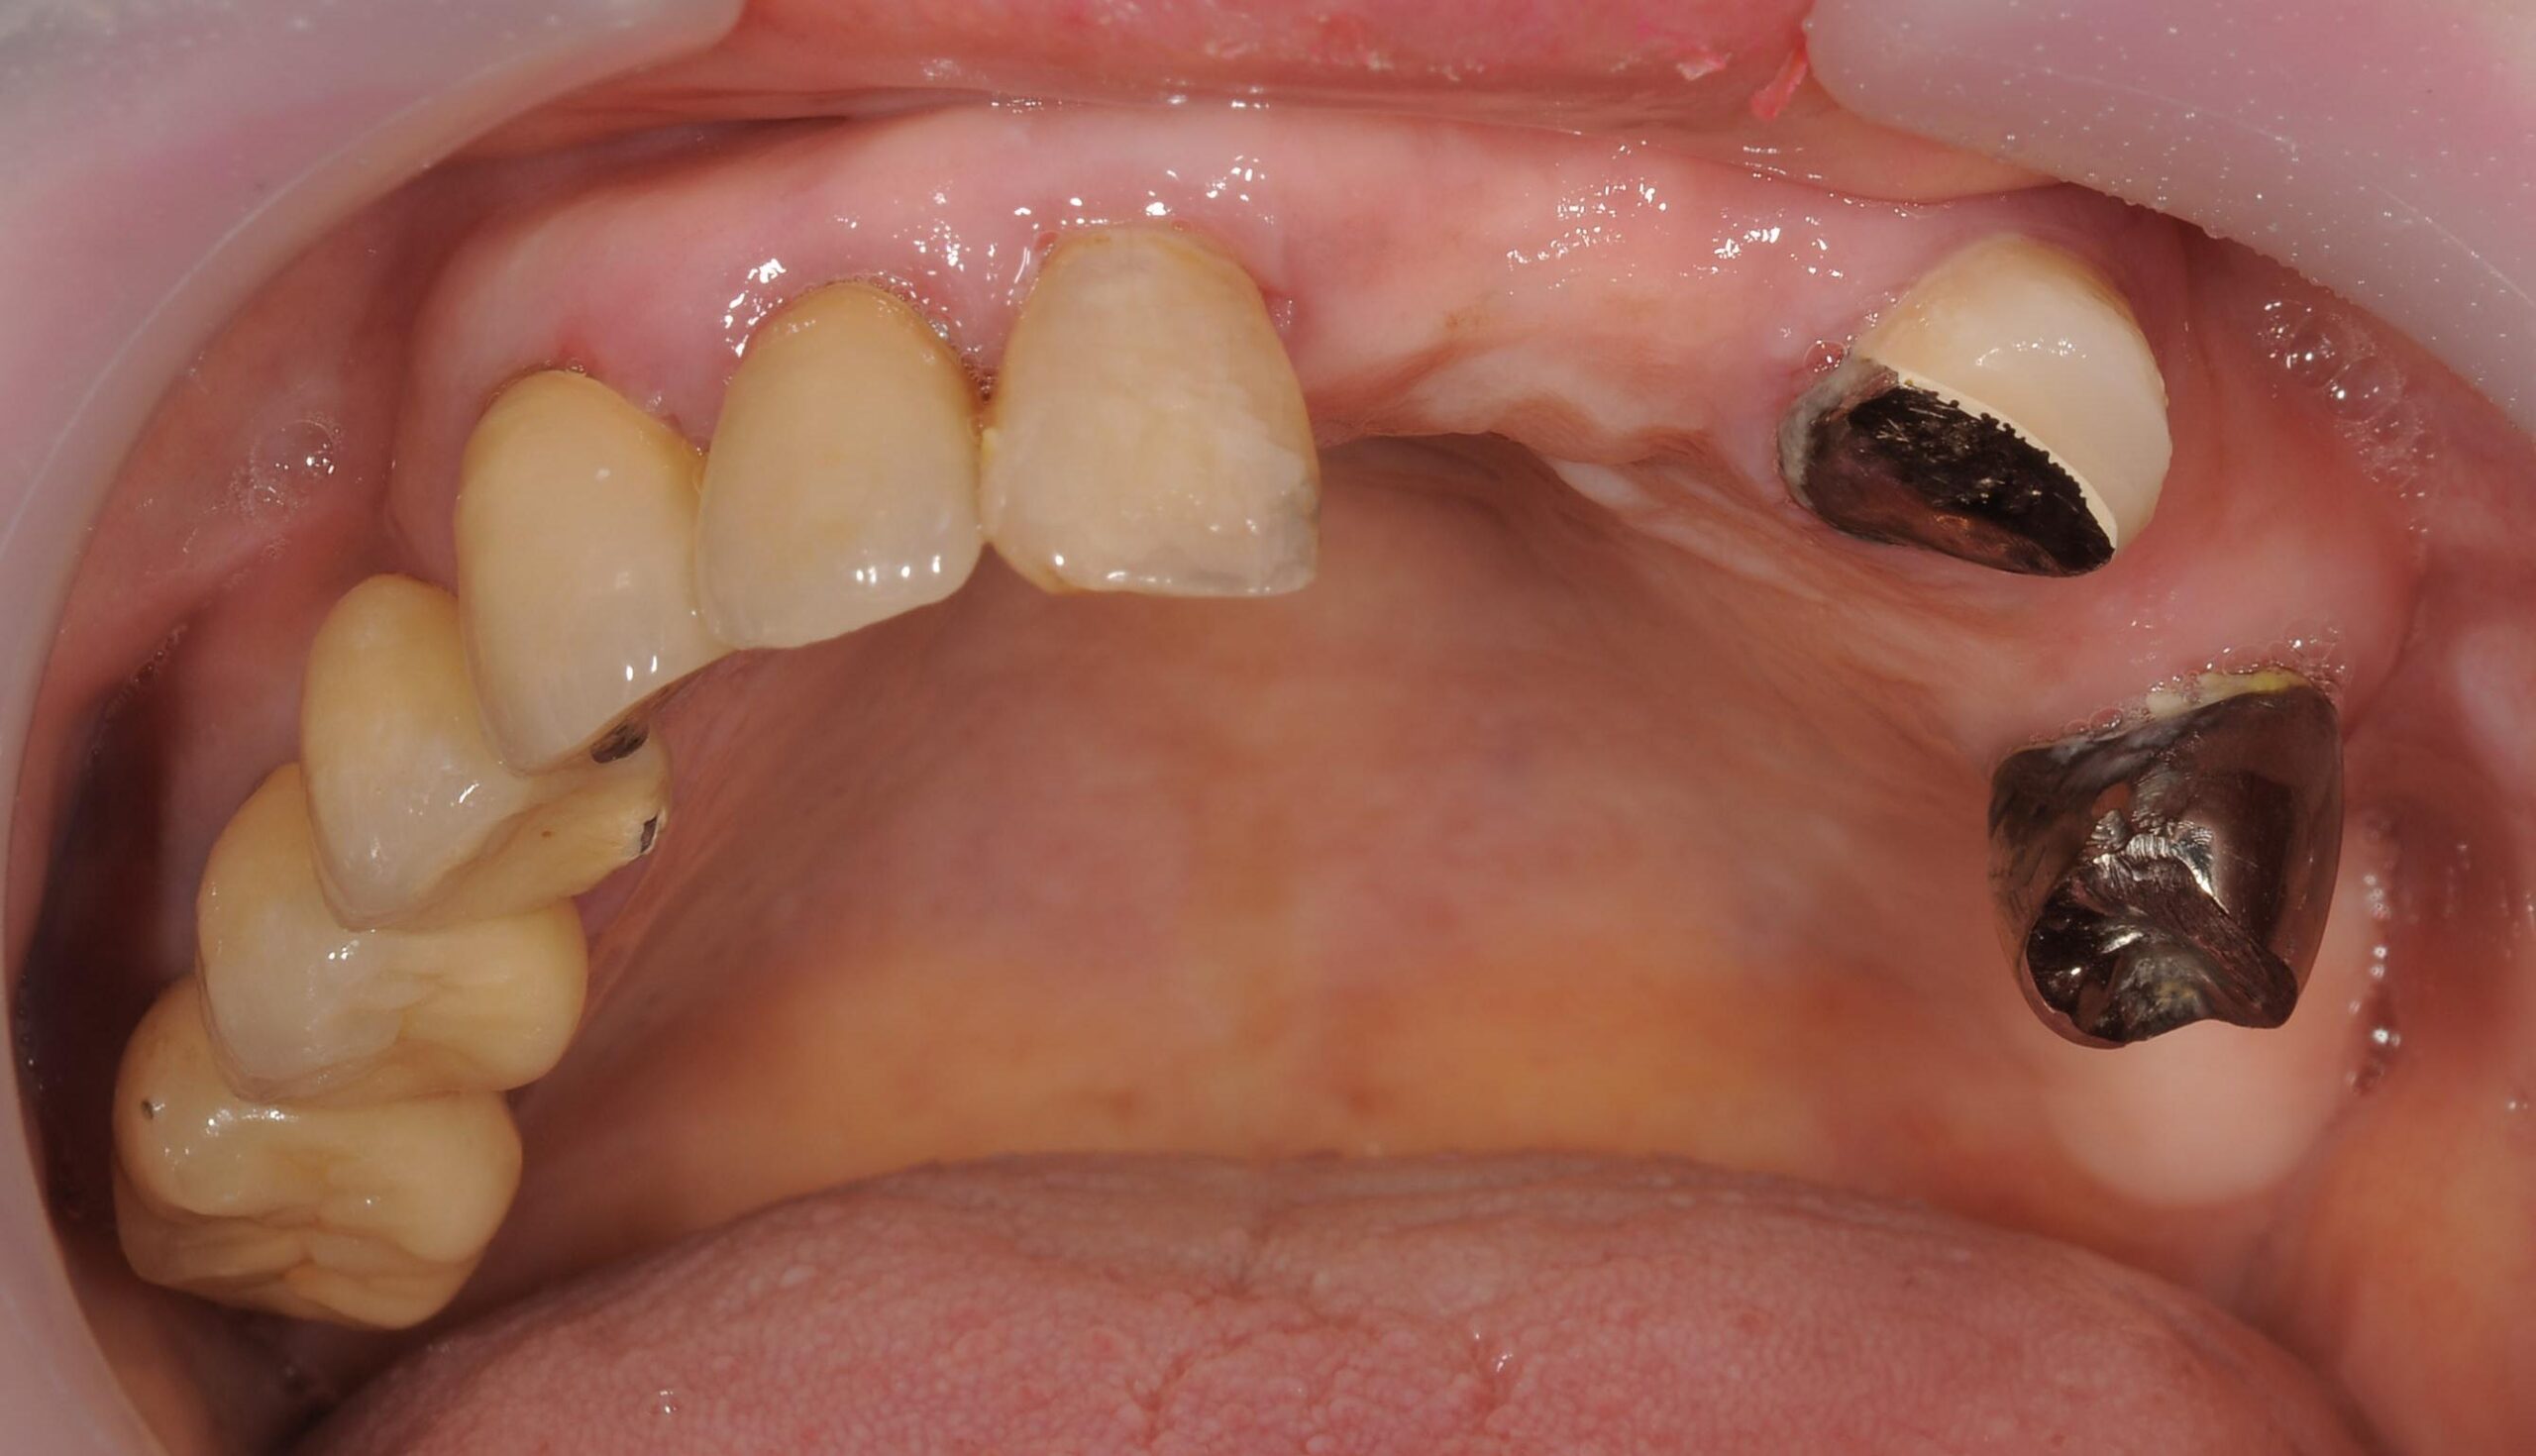

術前のパノラマレントゲン、下顎の骨は十分な高さが無いので下顎管を避けて傾斜埋入が必要でした。

歯の数が少なく、十分に咀嚼することが難しい状態です。